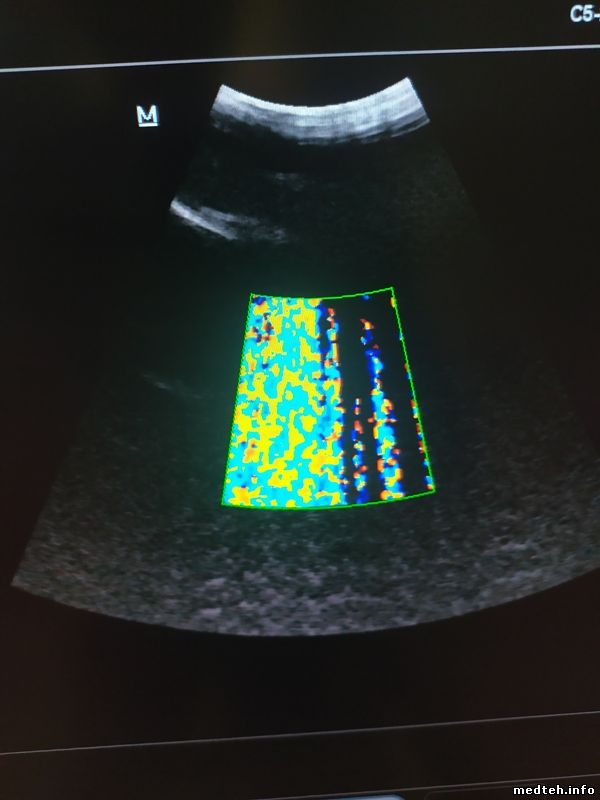

Помехи появляются при касании датчика по линзе, на ЦДК при этом помехи.

Датчик проверяли на двух разных УЗИ в разных районах.

Кто сталкивался с такими помехами? ...

8953008.jpg (40.7 Kb) · 7252899.jpg (37.9 Kb) · 0094548.jpg (47.8 Kb)